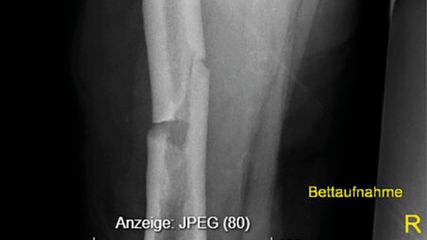

Atypische Frakturen & Bisphosphonate

Bisphosphonate sind Standard in der Osteoporosetherapie und wirksam in der Prävention osteoporotischer Frakturen. Allerdings sind sie in seltenen Fällen mit atypischen Frakturen, vor ...